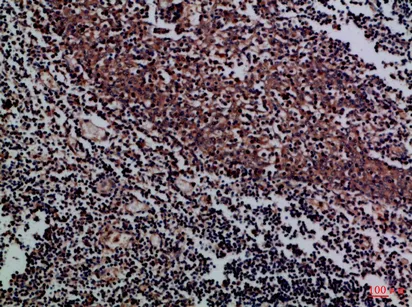

CD1A/B Rabbit Polyclonal Antibody($99/20μL)

Cat: APRab08259

Application:IHC-P,IF-P,IF-F,ICC/IF,ELISA

Reactivity:Human,Rat,Mouse

Gene Name:CD1A CD1B